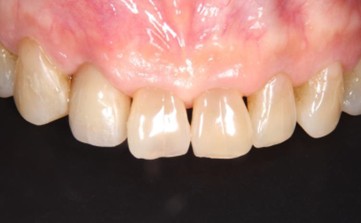

20代 男性

治療前

治療後

治療後- リスク・副作用

- 1年前に左上12 右上1の根の治療をし、その後放置していたら、左上2が破折した。

左上2インプラント補綴 左上1右上1オールセラミック装着。

歯根破折と虫歯による痛み、審美障害を主訴として来院。 - 検査方法

- コーンビームCT、レントゲン撮影

- 診断結果

- 左上2 歯根破折

- 治療詳細

- 左上抜歯後、インプラント埋入1本

骨造成あり 局所麻酔

インプラント治療後、左上1右上1セラミック修復2本 - 通院回数